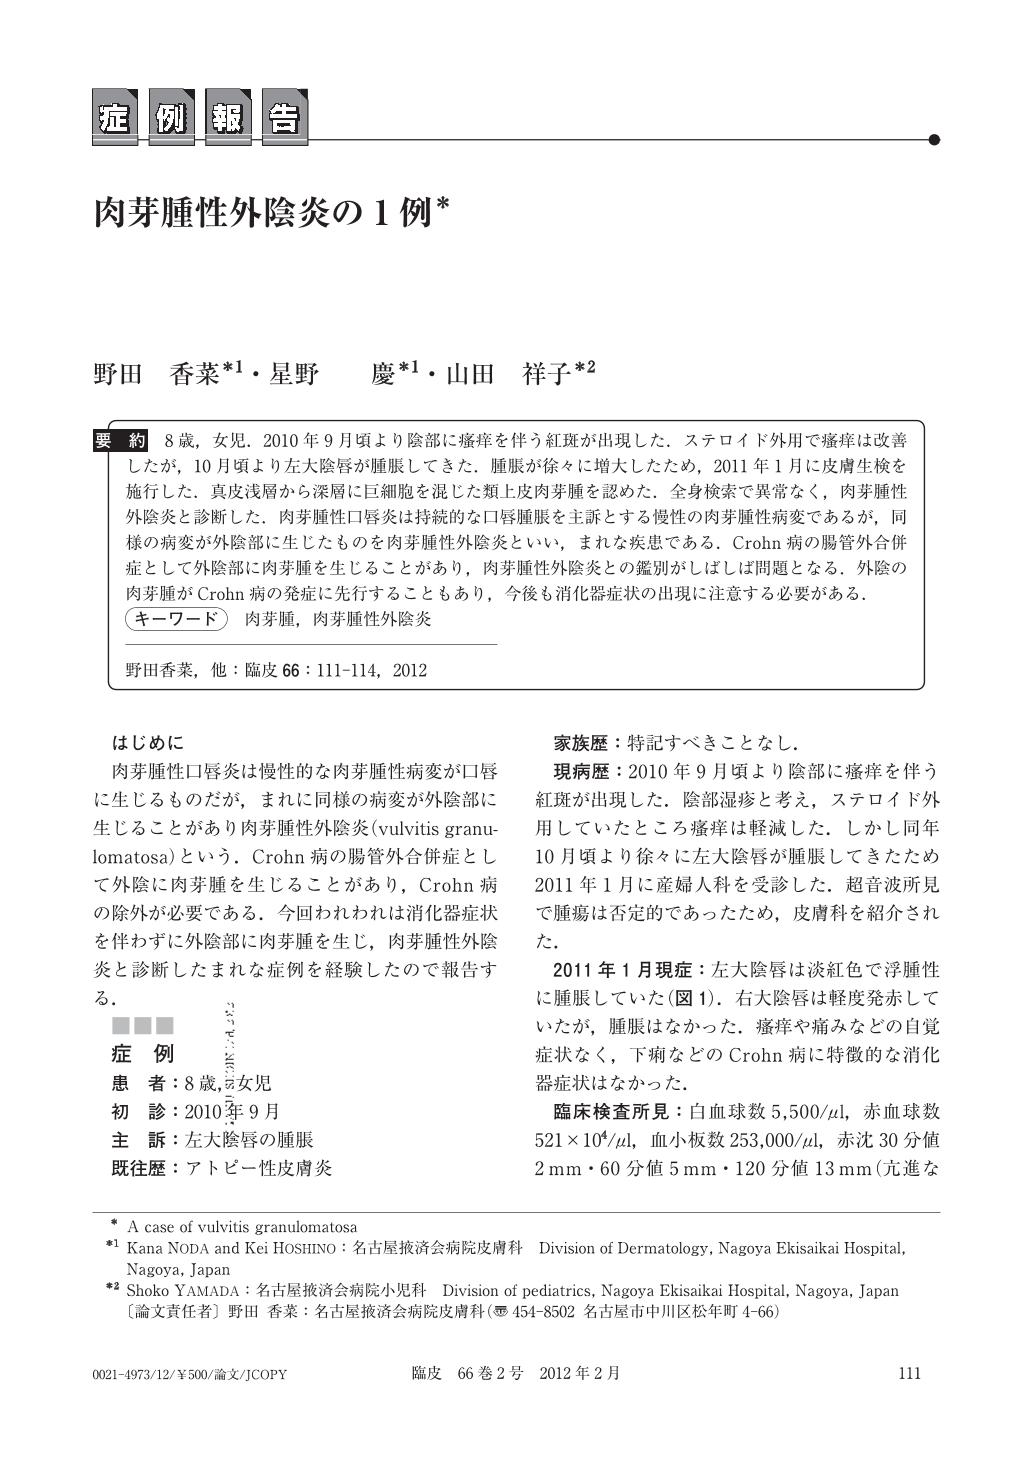

肉芽腫性外陰炎の1例臨床皮膚科 66巻2号医書.jp。